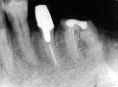

図3.術後2年 '88年4月。4」根管治療不備

による腫脹を主訴に再来。

図4.術後2年。'88年3月。4」の消炎処置 (歯根部掻爬、

HAP使用)後、E5CB│ブリッジ再製。

図9.64│初診時。'85年11月。 図10.64│3年経過。'88年4月。

4│根尖病巣悪化。

図11.4│根尖部掻爬 '88年4月。 図12.6│10年経過。 '95年1月。